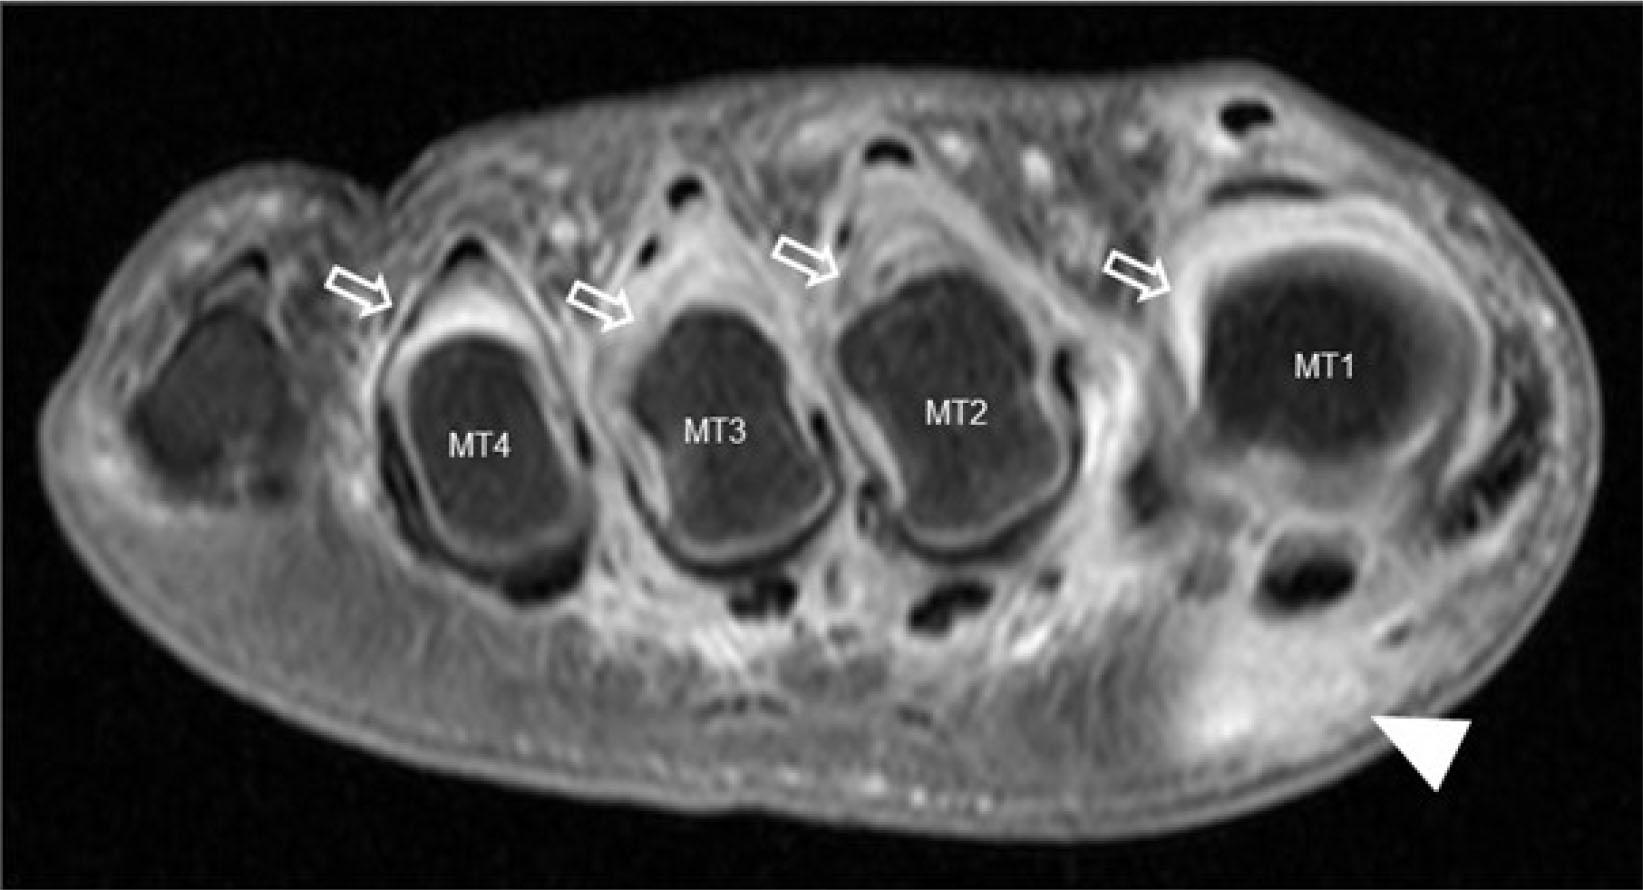

Lesser MTP joint plantar plate tear

Even more so than the 1st MTP joint, the plantar plates of the lesser MTP joints resist joint hyperextension and provide sagittal stability(11). Distally, the plantar plates are firmly attached to the proximal phalangeal bases while proximally, they are loosely attached to the metacarpal necks by fibro-synovial tissue(12). On either side, the plantar plates are firmly attached to the medial and lateral accessory collateral ligaments (Fig. 13) and, as such, co-existent injury of the plantar plate and accessory ligaments commonly occurs(12). Plantar plate tear can lead to MTP joint medial or lateral deviation, dorsal subluxation, and hammer toe(13). The normal plantar plate and plate tears are shown on US and MRI in Fig. 14 and Fig. 15. As with the 1st MTP joint, a midline hyperintense zone, measuring up to 2.5 mm long, at the phalangeal base is a normal anatomic recess(11) (Fig. 10). This is less frequently appreciated on US as a hyperechoic zone.

The 2nd, followed by the 3rd, MTP joint plantar plates are the most frequently injured(12). Plantar plate tears typically occur at the junction between the plantar plate and the accessory collateral ligament close to the phalangeal attachment, most commonly at the inferolateral aspect of the joint (Fig. 13). On US, most plantar plate tears are seen as discrete partial or full thickness hypoechoic defects in the plate substance(13,14). Flattening or attenuation may occur with plantar plate degeneration. When the plantar plate is completely torn, the flexor digitorum tendon may directly contact the metatarsal head(13,14). In the chronic setting, reactive pericapsular fibrosis can be seen as a non-compressible hypoechoic cuff of tissue abutting the plantar and inferolateral (or inferomedial) aspects of the MTP joint(13,14). US should be performed in both longitudinal and transverse planes, scanning the plantar aspect of the MTP joint slowly from lateral to medial and from distal to proximal, with angling of the transducer to avoid anisotropy. Most injuries occur at the distal attachment of the plate. Longitudinal US is best to detect and characterize tears while transverse US is useful to delineate the eccentric location of pericapsular fibrosis and to exclude subluxation of the flexor digitorum tendon. Longitudinal US during toe dorsiflexion can improve tear detection and appreciation of MTP joint subluxation(14).

For MR imaging, T1-weighted (T1W) coronal images are usually the most helpful as routine sagittal forefoot images do not always image the plantar plate in a true sagittal plane(12) (Fig. 15). Performing MRI in the prone position, with the foot in plantarflexion, results in less magic angle artifact and less movement artefact potentially facilitating assessment of the plantar plate(11). Prone positioning also leads to slight plantar shift of the interdigital soft tissues improving assessment of Morton’s neuroma(15). Dynamic US assessment during MTP joint dorsiflexion or during dorsal drawer (Lachman) testing can help assessment of plantar plate integrity and MTP joint stability. Compared with surgical findings, the pooled sensitivity (93%) of US for detecting plantar plate tears is comparable to that of MRI (89–95%), though MRI has a higher specificity (54–83%) than US (33–52%)(16). A negative US examination makes plantar plate injury very unlikely. If US is positive or equivocal, MRI can provide more specificity as to the nature of the injury and yield a more global assessment of the MTP joint(17).

Additional indirect MRI signs of plantar plate tear are joint effusion, subarticular BME, flexor tenosynovitis, an elongated 2nd metatarsal bone, and reparative pericapsular fibrosis while intermetatarsal bursitis and Morton’s neuroma are quite common accompaniments. Pericapsular fibrosis is a useful indirect sign of chronic plantar plate tear which often mimics Morton’s neuroma (i.e. ‘pseudoneuroma’)(11) (Fig. 16). Helpful features to distinguish between pericapsular fibrosis and Morton’s neuroma are listed in Tab. 3. It is likely that as pericapsular fibrosis/plantar plate tear becomes more widely recognized, less Morton’s neuromas and more chronic plantar plate tears will be diagnosed.